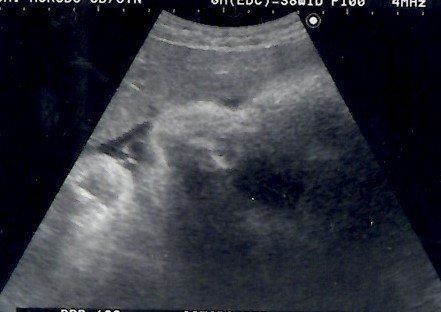

妊娠23週目のエコー写真 性別がほぼ確定

「性別は知りたいですか?」エコー画像を見ていた医師から問われて、「はい」と即答した私。しかし、告げられた性別は私が希望していたものではありませんでした。その日から数日間はかなり落ち込み、友人につい愚痴ってしまったほど。「赤ちゃんもおなかの中で聞いているよ。そんなこと言わないで」と友人からたしなめられ、ようやく我に帰りました。子どもを授かっただけでもうれしかった頃の気持ちを思い出して反省しました。